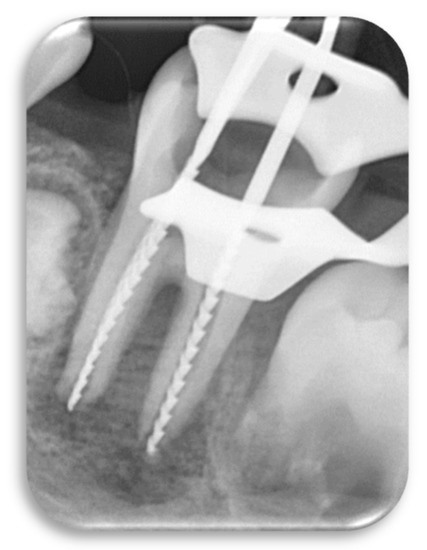

2.8. Biomechanical Preparation

2.9. Filling of the Root Canals